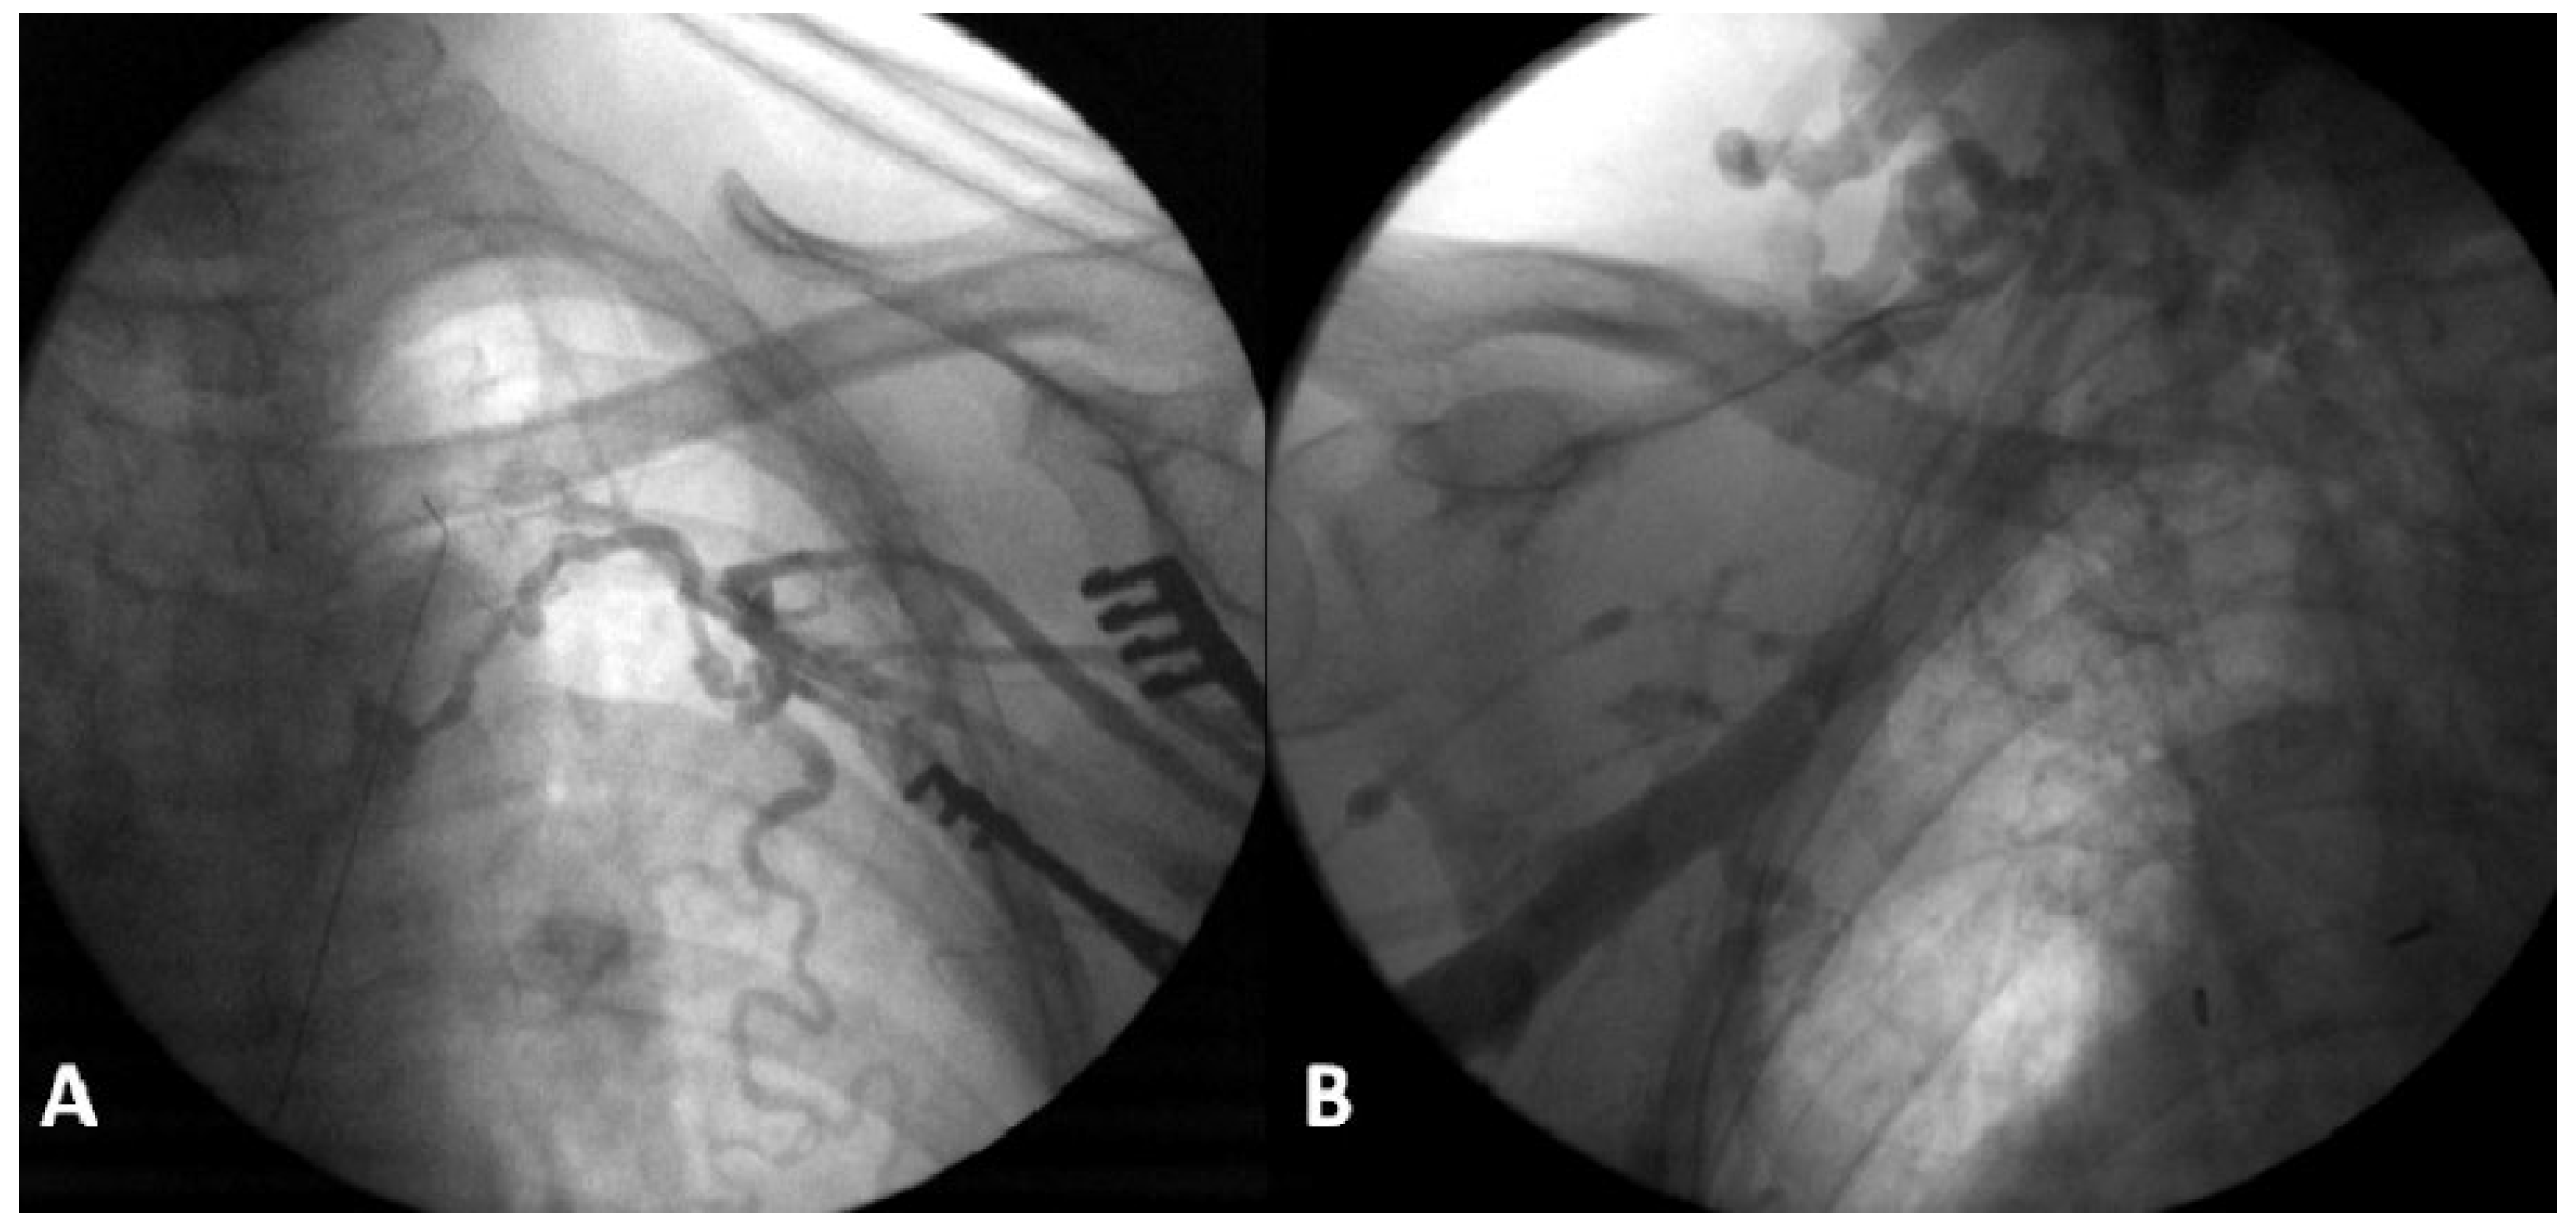

An initial approach via axillary and left subclavian venous puncture was attempted but was impossible owing to complete occlusion of this venous axis (Figure 1A). A venogram showed an occlusion of the right subclavian vein also (Figure 1B). Computed tomographic angiography indicated an obstruction of the superior vena cava and of the azygos arch with a collateral network draining through the azygos and hemiazygos network.

Figure 1. Obstruction of the left (A) and right (B) venous subclavian networks, visualised during intraoperative fluoroscopy.